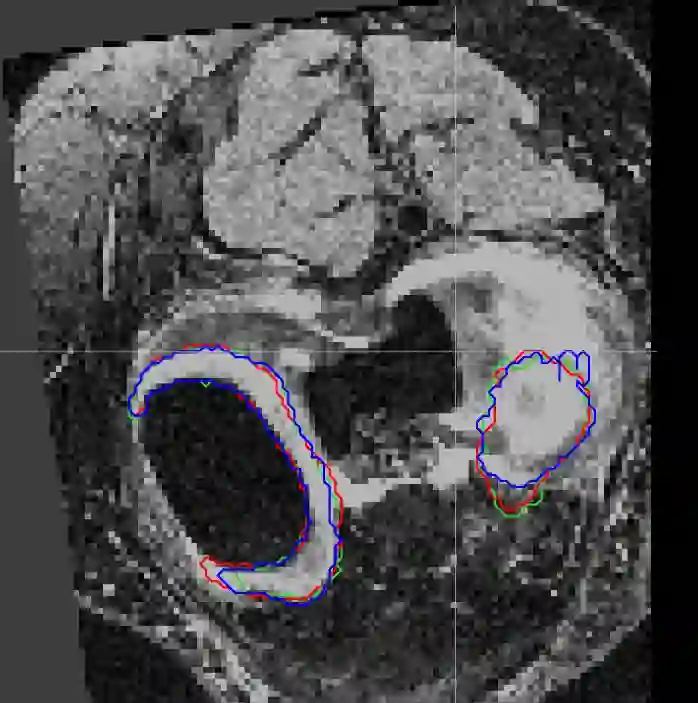

Direct automatic segmentation of objects from 3D medical imaging, such as magnetic resonance (MR) imaging, is challenging as it often involves accurately identifying a number of individual objects with complex geometries within a large volume under investigation. To address these challenges, most deep learning approaches typically enhance their learning capability by substantially increasing the complexity or the number of trainable parameters within their models. Consequently, these models generally require long inference time on standard workstations operating clinical MR systems and are restricted to high-performance computing hardware due to their large memory requirement. Further, to fit 3D dataset through these large models using limited computer memory, trade-off techniques such as patch-wise training are often used which sacrifice the fine-scale geometric information from input images which could be clinically significant for diagnostic purposes. To address these challenges, we present a compact convolutional neural network with a shallow memory footprint to efficiently reduce the number of model parameters required for state-of-art performance. This is critical for practical employment as most clinical environments only have low-end hardware with limited computing power and memory. The proposed network can maintain data integrity by directly processing large full-size 3D input volumes with no patches required and significantly reduces the computational time required for both training and inference. We also propose a novel loss function with extra shape constraint to improve the accuracy for imbalanced classes in 3D MR images.